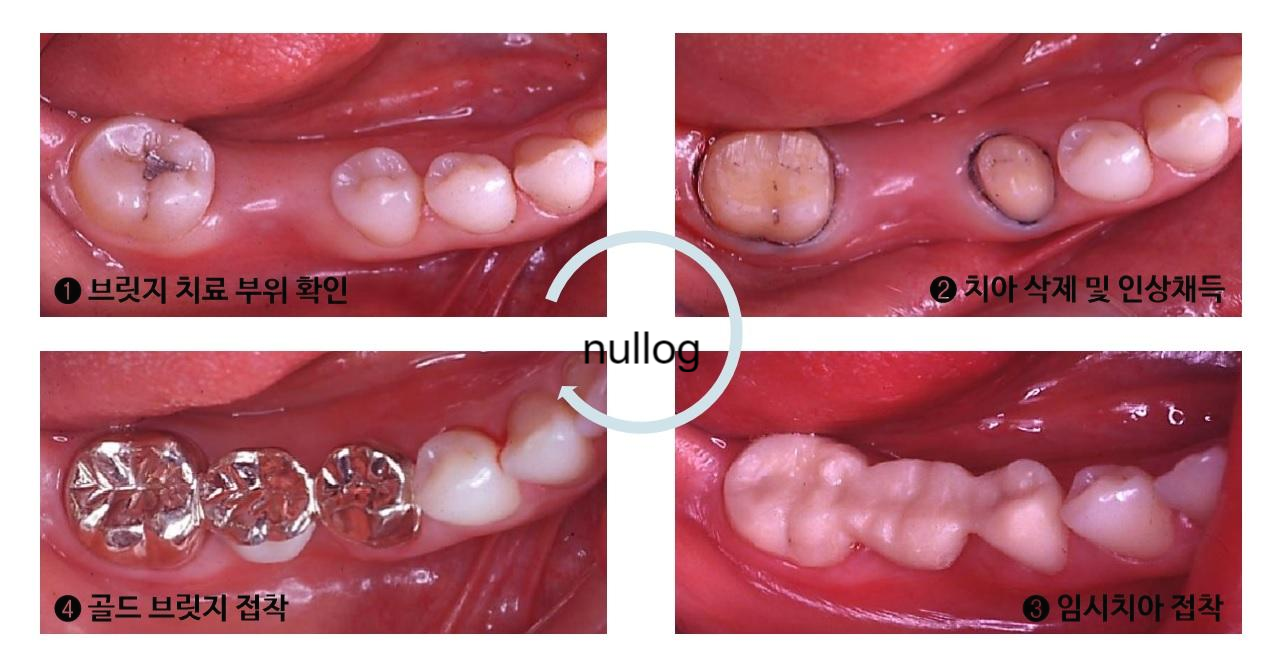

앞니크라운 통증으로 신사역치과춘치과의원에 내원하셨습니다. 4-유닛브릿지 아래쪽에 치근단염증이 확인됩니다.

치근 끝에 치근 끝 부분의 방사선 투과상 염증이 확인됩니다.